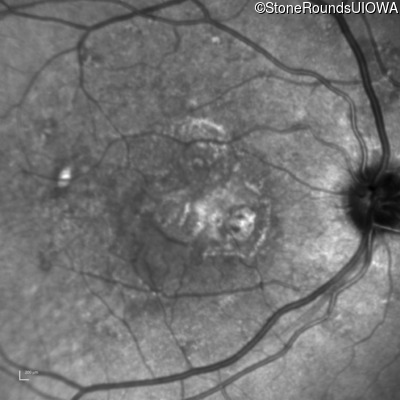

Fluorescein Angiography - Right - 20/250

Exemplar

Fluorescein Angiography - Left - 20/20